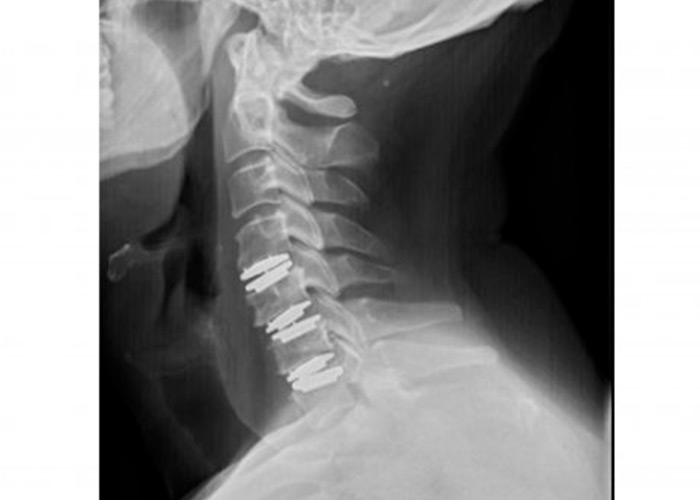

Tras haber probado todo tipo de tratamientos medico-rehabilitadores, el equipo de ICAC decide una intervención mediante técnica mínimamente invasiva y reconstrucción de los tres discos cervicales con prótesis móvil. La operación es un éxito y los resultados son notables inmediatamente.

protesis-cervical-movil-instituto-cac

Postoperatorio

En menos de 5 horas el paciente se recupera de la operación. Asimismo, la movilización del cuello comienza desde el primer momento y no se precisa collarín ni otros inmovilizadores.